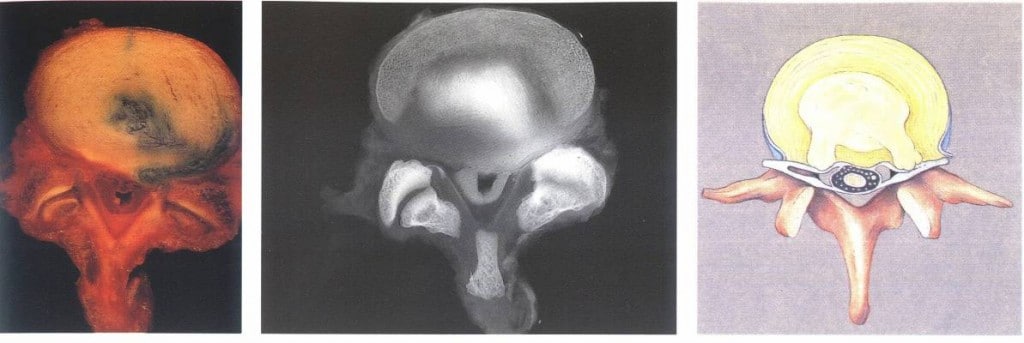

סכמת פריצת דיסק ולחץ על עצב פריצת דיסק וניוון מפרק חוליה ימני ב CT פריצת דיסק בניתוח

בלט הדיסק, בקע הדיסק או פריצת הדיסק מפעילים לעיתים קרובות לחץ וחיכוך על עצבים היוצאים בין חוליות עמוד השדרה וגורמים כאב מקרין לעכוזים ולרגליים. במקביל, גורם החיכוך לדלקת, חומציות ובצקת בסביבת העצב, הדיסק והחוליה.

הפגיעות בכריות הדיסק גם גורמות לפחיסת גובה כריות הדיסקים, לחיכוך מפרקי החוליות ולתהליך ניווני בו נוצרים זיזים סידניים על ידי השקעת סידן במוקדי הדלקת על ידי תהליכים אוטומטיים המתרחשים בגוף.

פחיסת גובה כרית הדיסק מוכחת בכירופרקטיקה על ידי צילומי רנטגן הנלקחים בעמידה ומאובחנים לפי מדידת קווי גובה בחוליות. סימון קוו הפחיסה הוא על שם החוקר מאק-נאב.